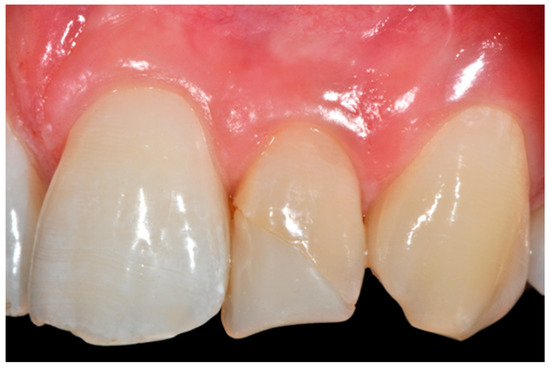

A wise balance of these opaque and translucent shades represents the key factor in obtaining reliable esthetic outcomes and great attention should be paid for their correct positioning [10,27]. Nevertheless, it happens that, during the restorative procedures, some inaccuracies could be made resulting in having opaque shades in place of translucent ones. This is generally realized too late, after finishing and polishing procedures thus compromising the final esthetic result [25]. In Figure 58 in fact the esthetic outcome of the left central incisor could have been improved if the opaque incisal margin had been made thicker and festooned. Conversely, we can notice from Figure 59 excessive thickness in the opaque incisal margin that, if not reduced, could provide an unpleasant final esthetic result.

Figure 58.

A more accurate management of the frame could have improved the thin and not festooned incisal opaque margin on left central incisor.

Figure 59.

Completing the restorations without previously reducing the incisal frame could provide an unpleasant final esthetic outcome.